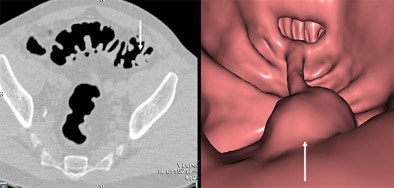

![]() |

| A 12-mm tubular adenoma in the sigmoid colon is seen in both 2D (left) and 3D (right) (Vitrea, Vital Images) CT images obtained in a male patient in his 50s. The patient was referred for virtual colonoscopy following incomplete colonoscopy. Images courtesy of Dr. Michael Macari. |